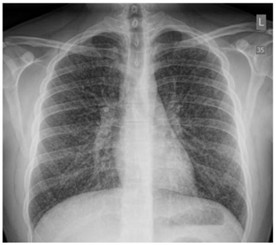

Pulmó crispetes de blat de moro.

Font: Pubmed